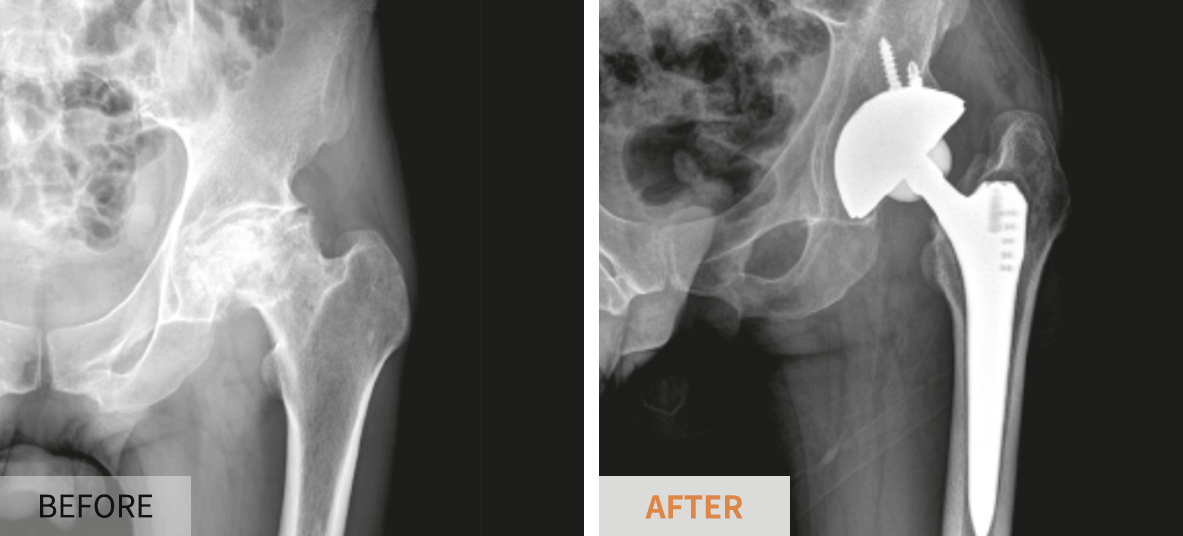

- 인공관절 치환술: 가장 일반적인 고관절 수술입니다. 퇴행성 관절염이나 심한 외상으로 인해 고관절이 손상된 경우, 인공 관절로 대체합니다. 이 수술은 대개 1-2시간 가량 소요되며, 회복이 길어질 수 있습니다.

각 수술 방식에 따라 환자의 상태를 고려한 특화된 치료 계획이 필요합니다. 예를 들어, 인공관절 치환술을 받을 경우에는 십여 주의 회복 기간 동안 물리 치료와 약물 치료가 반드시 포함되어야 합니다. 반면 관절경 수술의 경우에는 초기 회복 단계에서의 가벼운 운동과 체중 부하가 더 강조될 수 있습니다.

- 진단적 검사: 의사가 필요할 경우 정기적으로 X-ray나 MRI를 통해 관절의 상태를 체크할 수 있습니다.